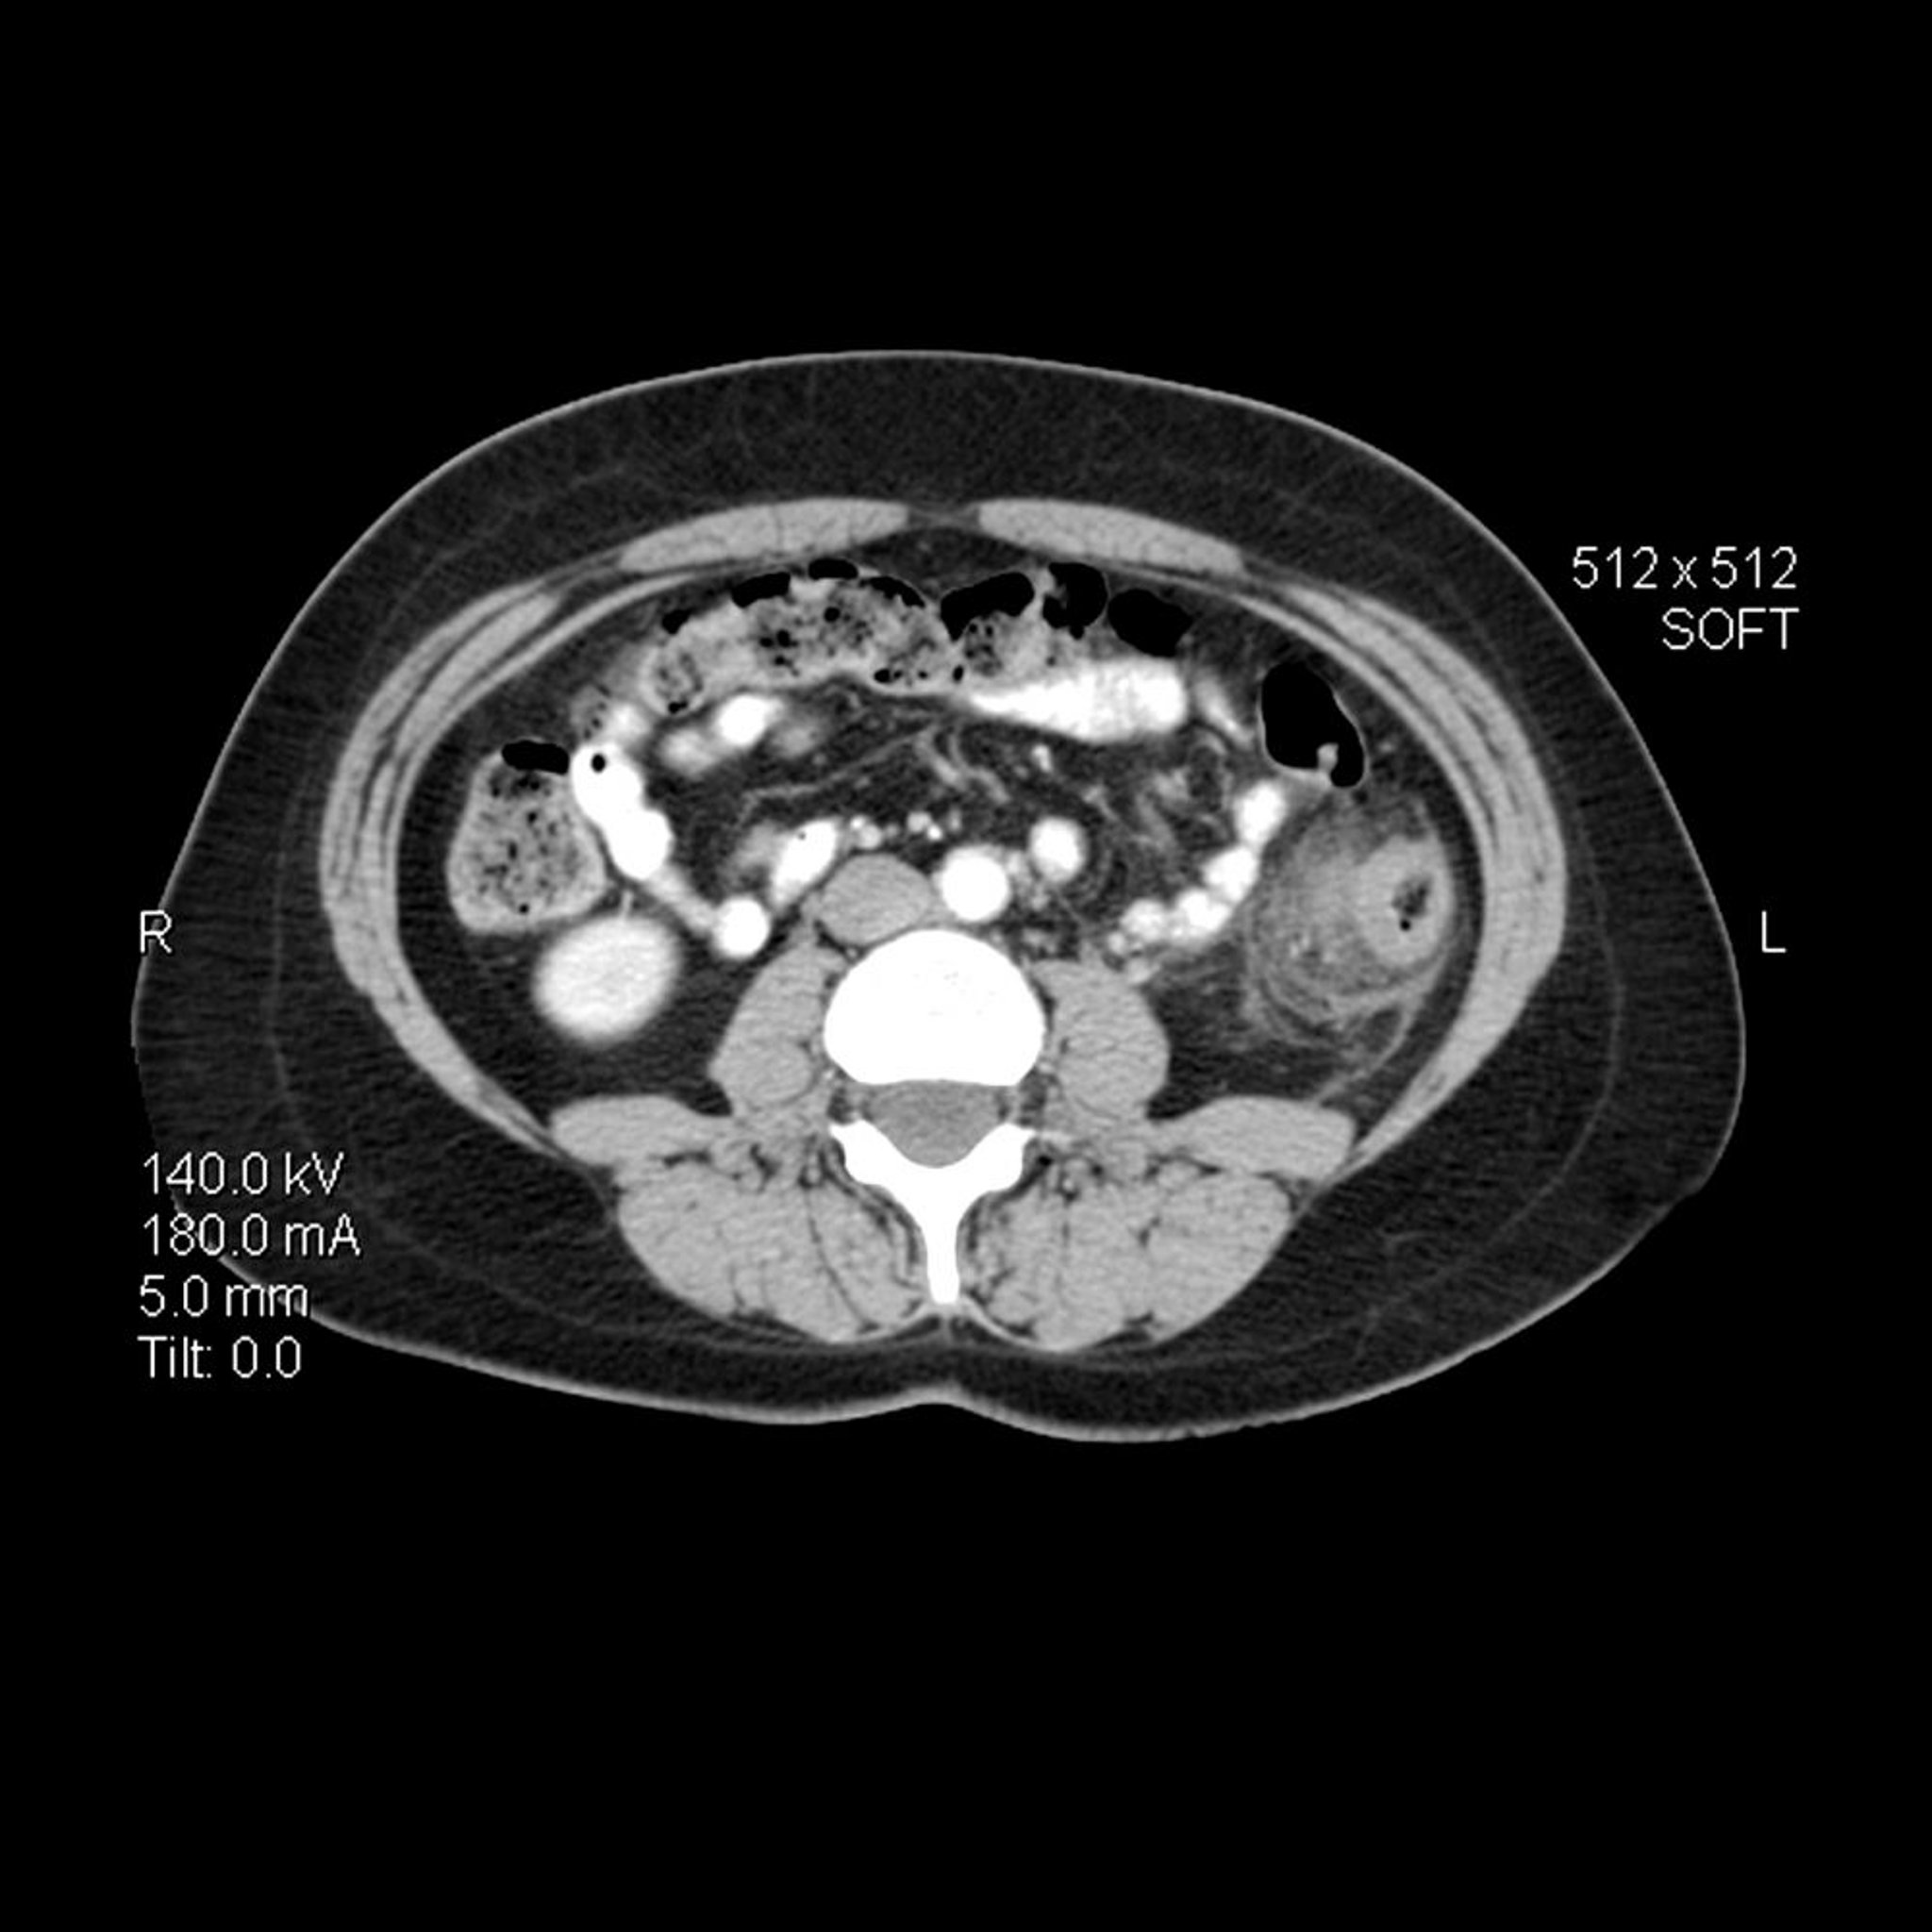

Diverticulite (TC)

Nessa imagem de TC axial (transversal) do abdome em uma pessoa com diverticulite, a parede do colo descendente está espessada. Há também estrias inflamatórias com aumento da densidade na gordura pericolônica adjacente.

LIVING ART ENTERPRISES, LLC/SCIENCE PHOTO LIBRARY